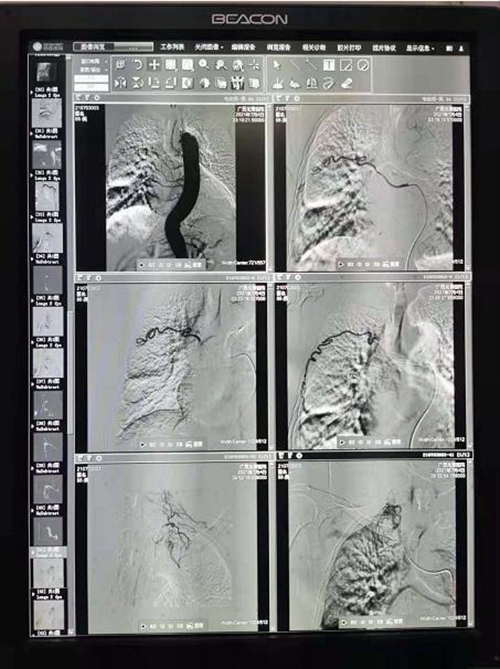

“俸医生,66床患者发生大咯血,快过来抢救”!7月4日凌晨,胸心外科病房内传来护士焦急的呼救。主管医生俸成钢接到呼救后,第一时间冲到病房。此时的66床患者黄大爷面色苍白,不断有血液...